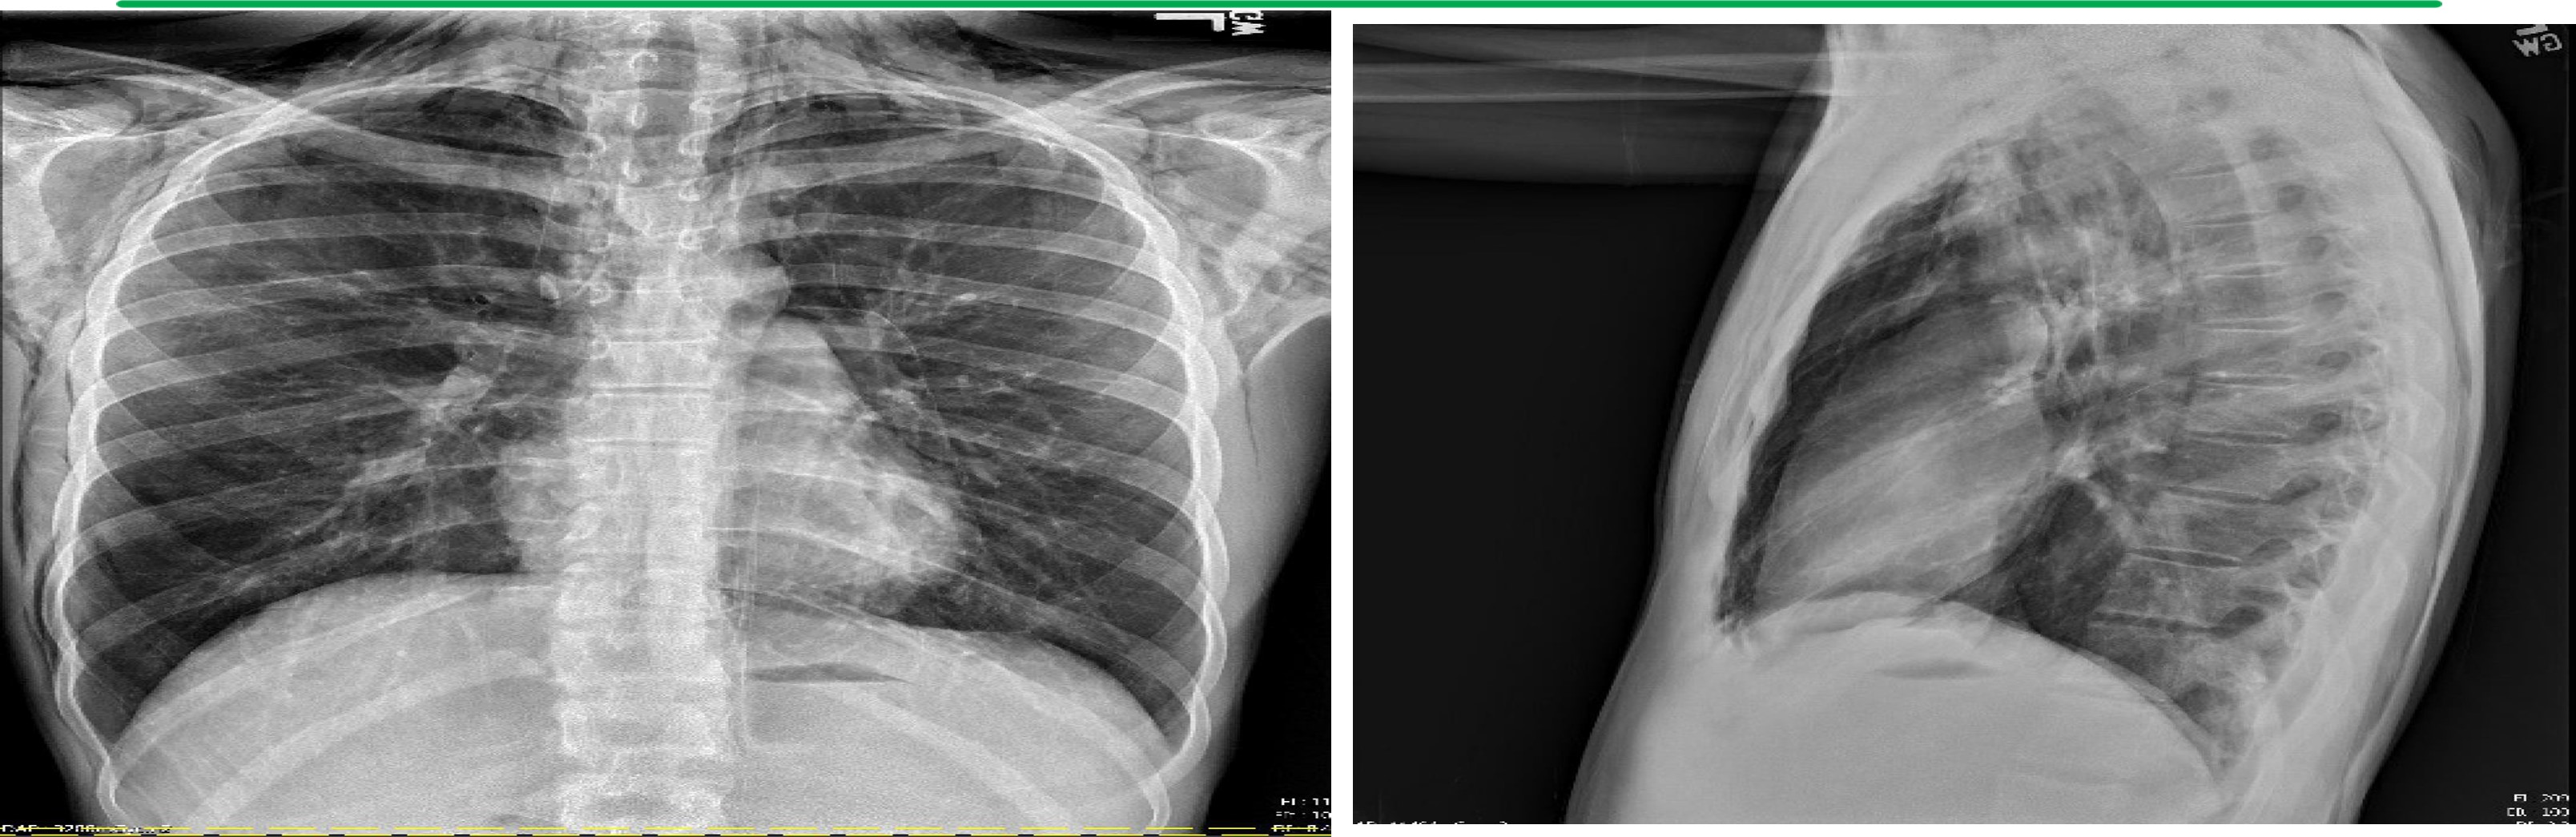

Anterior-Posterior (AP) and Lateral Chest X-ray

Findings: There is extensive pneumomediastinum with air dissecting along the esophagus, mediastinum, and supraclavicular soft tissues, along the lateral chest wall bilaterally, greater on the right.

No definite pneumothorax is visualized.

There is no focal consolidation. There is no pleural effusion. The heart size is normal. The bones are unremarkable.

Impression: Marked pneumomediastinum with air dissecting across the soft tissue planes.